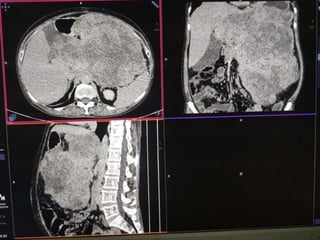

 55 yr old female patient

 Presented with complaints of lump abdomen and vague

abdominal discomfort

 Bowel habits normal with no other gastrointestinal complaints

CASE 2

CASE2

DIFFERENTIALS

Diagnosis Points in favour Points against

Retroperitoneal

sarcomas

• Leiomyosarcoma

/Undifferentiated

Liposarcoma

• MFH

Age and clinical

presentation

Imaging features

(Large ill defined

heterogeneously

enhancing lesion

with areas of

necrosis)

No fat density/

calcification

No calcification

GIST Age

Biopsy:

 Poorly differentiated Leiomyosarcoma